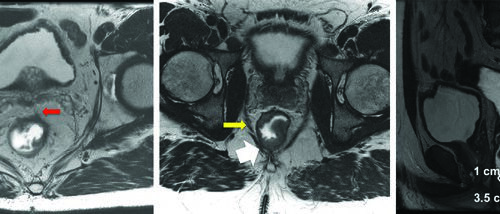

Delineamento de Volumes

Guias práticos de delineamento de volumes-alvo e órgãos de risco por sítio anatômico na radioterapia.